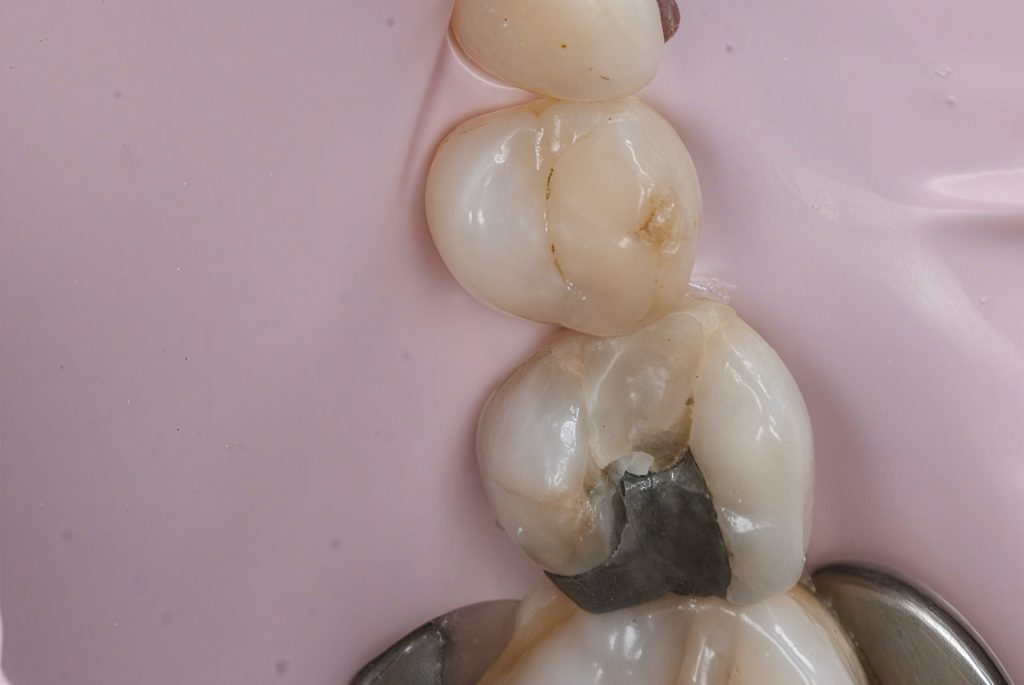

Defective composite and caries were removed in a controlled manner preserving sound enamel walls. Teflon floss ties and wooden wedges used for separation and gingival retraction (Fig 3–6).

3. Matrix System Placement

Sectional matrix system used to recreate anatomical proximal walls. Ring stabilization applied to ensure tight contact and optimal emergence profile (Fig 7–8).

- Proximal clearance and wedge placement

- Matrix placement and isolation refinement

- Sectional ring application